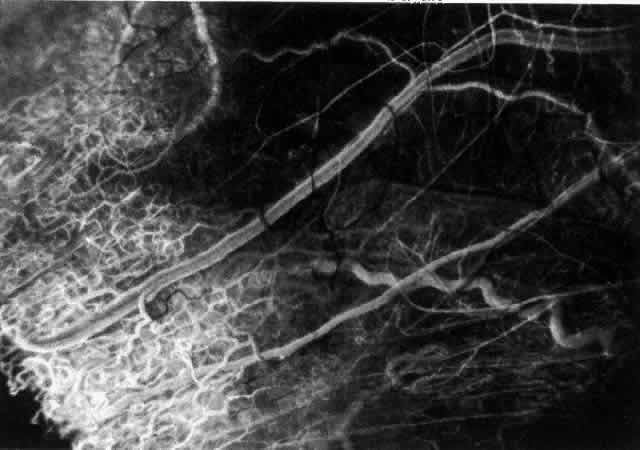

The characteristic features of necrotizing scleritis on fluorescein angiography are hypoperfusion and, eventually, nonperfusion of the vascular networks (Figs. 40 through 43).26 The initial changes are on the venous side of the capillary network; the transit time of the dye increases even if the eye is red and congested. If the disease process persists or has been present for a long time, thrombosis and permanent vaso-occlusive changes occur. These vessels (or the occluded capillary network) are bypassed by the opening of anastomotic channels. New vessels in a granuloma give rise to deep intrascleral leakage of dye (see Fig. 43). Conjunctival and episcleral involvement by the destructive change is late but is always preceded by vaso-occlusive changes that can sometimes be detected with use of the red-free light on the slit lamp (Figs. 44 and 45).

Fig. 40. Early necrotizing scleritis. There is characteristic yellow discoloration of the sclera underlying the conjunctiva at a point of necrosis. In this instance a small filament of tissue has penetrated the conjunctiva.

Fig. 41. Late stage of fluorescein angiogram adjacent to the site of necrosis in the same patient as in Figure 40. Although the eye is uniformly congested, the area near the necrosis shows vascular shutdown, whereas the rest of the conjunctiva and episclera is normally perfused.

Fig. 42. Late arterial phase of fluorescein angiogram in a patient with necrotizing scleritis. All the vessels except the main trunk and the vessels around the limbal perforating vessels are occluded and remain unperfused throughout the angiogram.

Fig. 43. Late venous phase of angiogram of a patient with necrotizing scleritis showing late deep leakage from vessels on the surface of the sclera and leakage of the capillary network at the limbus and the vessels draining it, together with poor or absent perfusion of the remaining vessels.